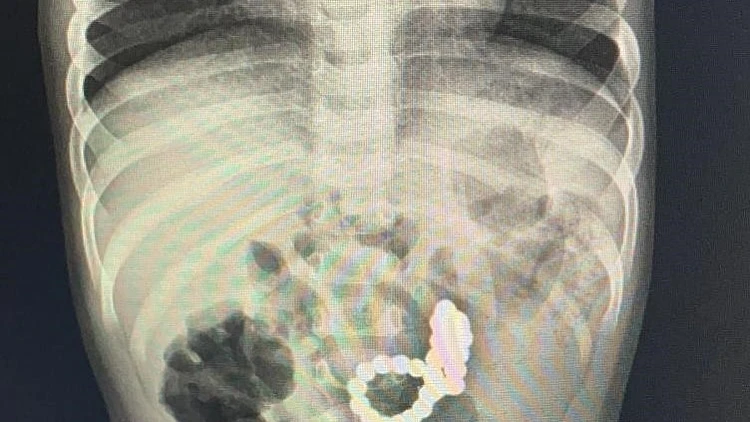

צילום הרנטגן גילה: מחרוזת בגופו של פעוט כבן שנה

לחרדתם של אנשי הצוות, הצילומים הראו מעין מחרוזת המונחת במעיים של הפעוט. לדברי ד"ר פרסמן, "זה נראה כמו מחרוזת, אבל אנחנו כבר למודי ניסיון ממקרים מרובים של בליעת מגנטים שטיפלנו בהם בתקופה האחרונה והבנו מיד שמדובר במגנטים מסוכנים. מכיוון שההורים לא ידעו להעריך כמה זמן המגנטים הללו נמצאים בבטנו של הילד הבנו שאין לנו זמן מיותר וחייבים להיכנס איתו כמה שיותר מהר לחדר ניתוח. המגנטים האלו זו סכנת חיים ממש".